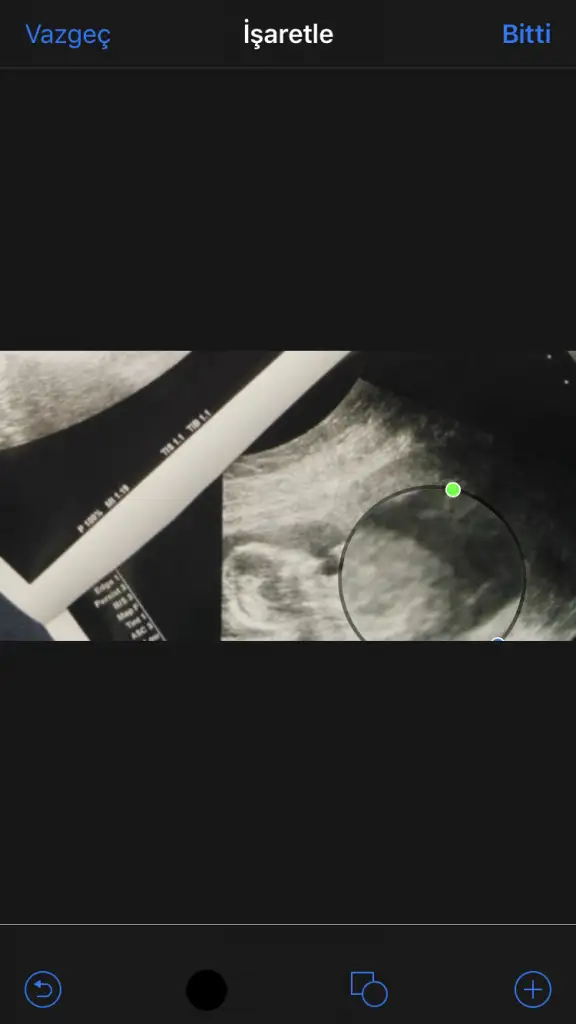

Buda bizim Nub umuz bı tahminde bulunur musunuz ☺️ bıraz karanlık cıktık ama olabıldiği kadar. Dr erkek dedı ilerleyen zamanda netlestırrız dedı. Sızcede oylemı tesekkürler .